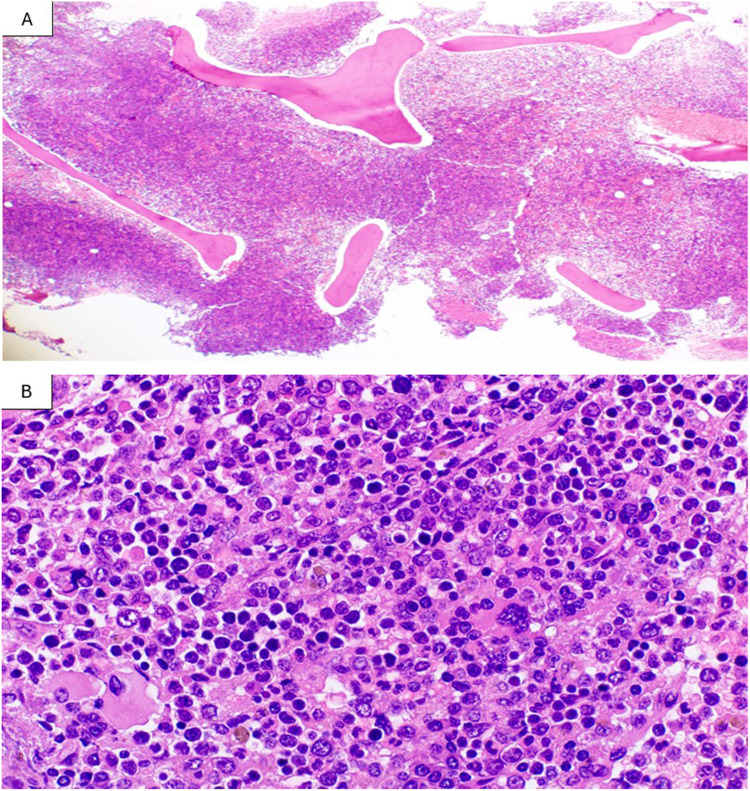

髓母细胞白血病(MML)表现为慢性髓系白血病(CML)的母细胞期表现是非常罕见的,文献中记录的病例有限。了解其独特的临床病理特征和治疗结果对优化患者管理至关重要。45岁男性,2016年起有CML病史,既往接受伊马替尼和达沙替尼治疗,治疗中断后出现白细胞增多(WBC 27.3 × 103/μL), 58%循环母细胞呈偏色肉芽。骨髓检查显示30%的母细胞CD117和胰蛋白酶阳性。流式细胞术鉴定出两种不同的群体:7%的成髓细胞和27%的未成熟髓细胞具有明亮的CD117表达。BCR-ABL1重排比例为112% (IS)。患者接受标准“3 + 7”诱导化疗和达沙替尼联合治疗。尽管有发热性中性粒细胞减少症的并发症,诱导后的骨髓检查显示完全的形态缓解。本病例强调了在CML母细胞期使用强化联合治疗成功的初始治疗髓母细胞转化。详细的形态学、免疫表型和分子特征为这种罕见的实体提供了有价值的见解,而良好的初始反应支持积极的治疗方法。需要长期随访和进一步研究来确定最佳治疗策略。

Myelomastocytic leukemia (MML) presenting as a blast phase manifestation of Chronic Myeloid Leukemia (CML) is exceptionally rare, with limited documented cases in the literature. Understanding its distinct clinicopathologic features and treatment outcomes is crucial for optimal patient management. A 45-year-old male with a history of CML since 2016, previously treated with imatinib and dasatinib, presented after treatment interruption with leukocytosis (WBC 27.3 × 103/μL) and 58% circulating blasts showing metachromatic granulation. Bone marrow examination revealed 30% blast cells with strong CD117 and tryptase positivity. Flow cytometry identified two distinct populations: 7% myeloblasts and 27% immature myeloid cells with bright CD117 expression. BCR-ABL1 rearrangement was confirmed with a ratio of 112% (IS). The patient received combination therapy with standard "3 + 7" induction chemotherapy and dasatinib. Despite complications of febrile neutropenia, the post-induction bone marrow examination demonstrated achievement of complete morphologic remission. This case highlights the successful initial treatment of myelomastocytic transformation in CML blast phase using intensive combination therapy. The detailed morphologic, immunophenotypic and molecular characterization provides valuable insights into this rare entity, while the favorable initial response supports an aggressive treatment approach. Long-term follow-up and further studies are needed to establish optimal treatment strategies.